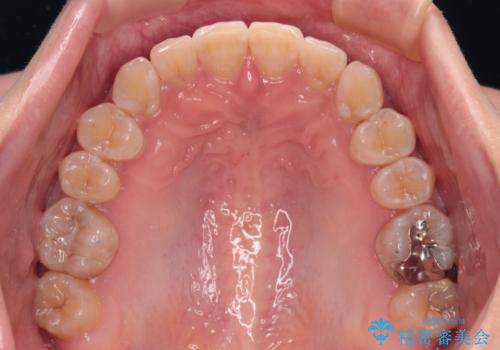

【モニター】下顎前歯のデコボコをインビザラインできれいに

- 下顎の八重歯を気にして来院された患者様です。

マウスピース矯正でもワイヤー矯正でも対応可能であり、マウスピースによる治療を希望されたため、インビザラインを用いることとしました。

下顎前歯にデコボコが集中していたため、顎間ゴムによる後方移動とIPR(歯と歯の間を削ること)により歯列を整えることとしました。

下顎前歯のデコボコが集中しており、奥歯の咬み合わせは、上顎に対して下顎が前方位にある状態でした。下顎の歯列を後方へ移動させる治療はインビザラインの得意とするところですので、1年程度で無事に治療を終えることができました。